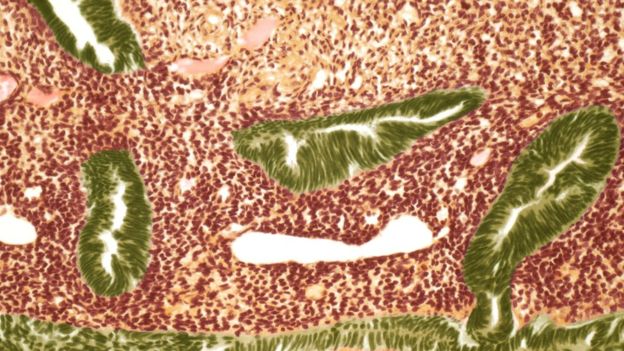

تصوير مقطعي لخلايا سرطانية في الرحم